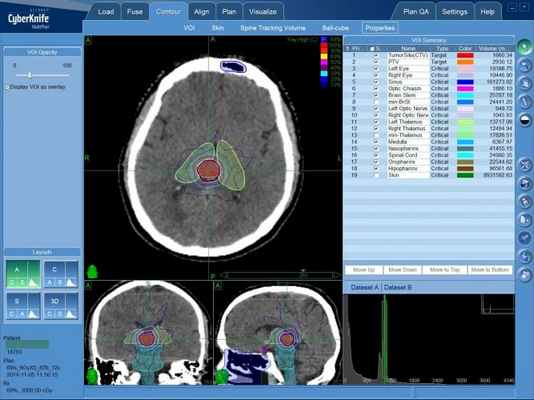

Лечение на системе КиберНож

В случае раннего диагностирования новообразования, а также небольшого размера опухоли эпендимомы, возможно проведение дистанционного лечения — радиохирургической операции на системе КиберНож.

Для этого в процессе планирования лечения определяется требуемая форма и расположение объема, в котором будет сформирована зона равномерно высокой дозы ионизирующего облучения — она будет полностью совпадать с указанными лечащим врачом контурами опухолевого поражения. Составленная на основе данных КТ- и МРТ-исследований пространственная 3D-модель с указанием зон с минимальной и максимальной лучевой нагрузкой, передается в программный комплекс КиберНожа для расчета множества последовательно подаваемых с различных положений тонких лучей ионизирующего излучения. После этого пациент может начинать лечение эпендимомы на КиберНоже.

Лечение эпендимомы головного мозга на КиберНоже

При радиохирургии на КиберНоже не требуется специальной подготовки пациента, наркоз не проводится — пациент во время фракции (сеанса) лечения эпендимомы на КиберНоже находится в сознании. Роботизированная “рука”-манипулятор комплекса последовательно занимает указанные в плане лечения положения, в каждом из которых производится подача отдельного тонкого пучка ионизирующего излучения. После завершения фракции (15-30 минут) пациент сразу может вернуться к обычному распорядку своего дня. Количество фракций зависит от множества индивидуальных факторов.